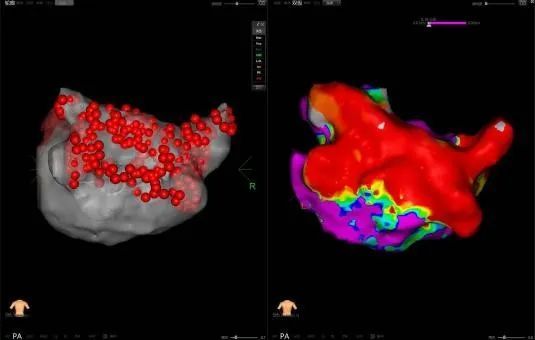

PFA是一種創新且有前景的微創、安全和高效的新興治療方法,通過瞬時的高電壓脈沖電場直接作用于心肌細胞,以不可逆電穿孔機制消融心臟組織,有效的隔絕異常激動及異位傳導路徑,從而恢復正常心律。PFA具有獨特的消融組織選擇性、消融時間極短、無熱損傷炎性水腫和附帶周圍組織損傷并發癥等特點,是現有技術中針對心律失常更理想的消融手段,可大大減少因傳統消融存在手術并發癥風險及消融不足導致房顫復發的風險。與傳統的射頻導管消融或冷凍球囊消融相比,脈沖電場消融手術具有更加安全、消融效率高、并發癥少等諸多優點,徹底改變了房顫治療的格局,為房顫患者帶來更好的治療方案,帶來更多治愈的希望。

此次手術患者均為持續性房顫患者,由延安大學咸陽醫院吳棟梁院長、心律失常專家劉雄濤副院長帶領介入團隊開展,安全高效、圓滿完成手術,手術過程患者全程清醒,術中自訴感覺良好,無痛苦感受。術后患者的心律恢復并維持了竇律,目前恢復情況良好,無任何并發癥出現。